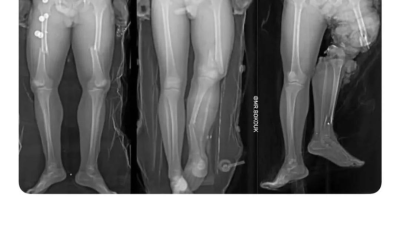

교통사고 났을 때 자세별 부상차이